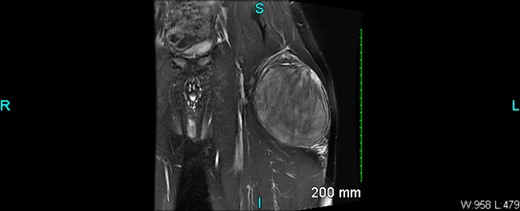

An X-ray of the left femur was negative. An ultrasound revealed abnormal findings, and an MRI with and without IV contrast showed a 10.5 × 7.1 × 11.4 cm heterogeneous enhancing mass within the vastus lateralis muscle without osseous invasion (Figs 1 and 2). There were islands of fat versus hemorrhage within the mass. The overall findings were non-specific but favored a sarcoma.

The case also highlights the importance of imaging in the diagnosis of ASPLT. In this case, an X-ray of the left femur was negative, but an ultrasound revealed abnormal findings, and an MRI showed a heterogenous enhancing mass within the vastus lateralis muscle without osseous invasion. These findings were non-specific but favored a sarcoma [2].